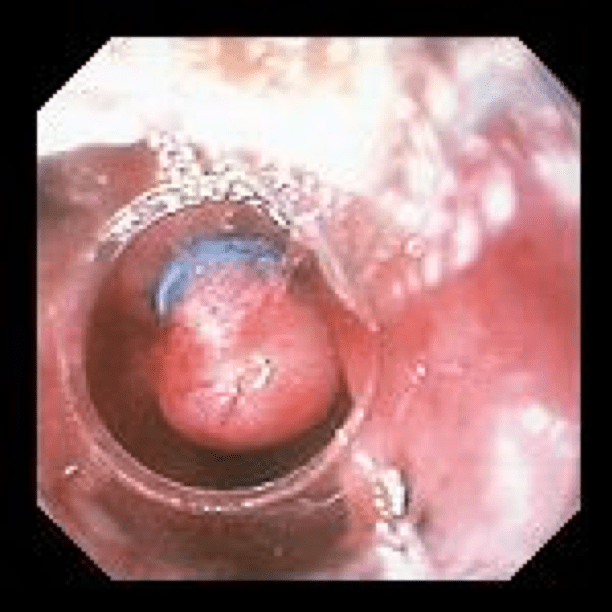

Therapeutic procedures that can be done during endoscopy are:

- Banding of varices